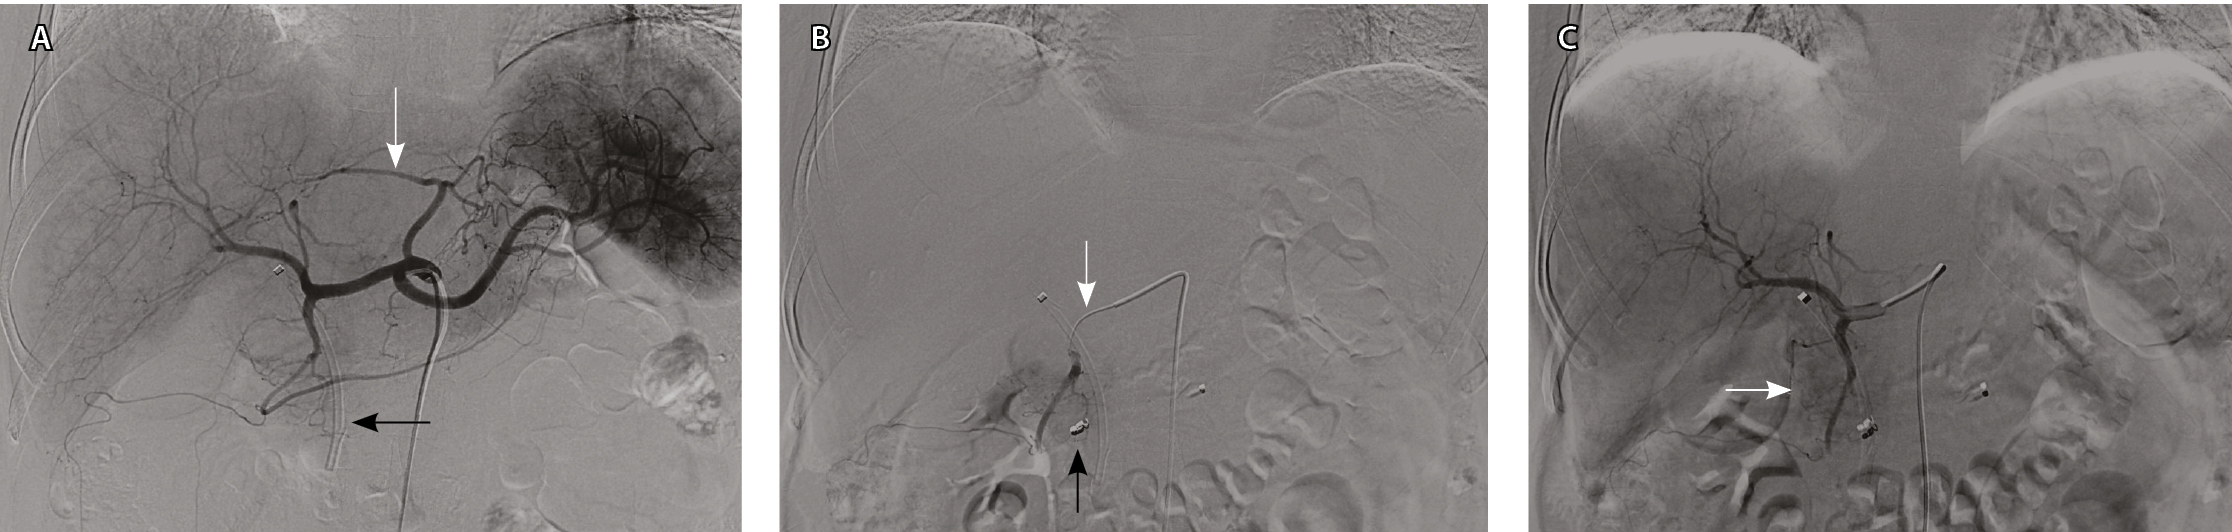

Конформную дистанционную ЛТ проводили на линейном ускорителе Elekta Axesse (Elekta, Швеция) с энергией 6 МэВ в многопольном статическом режиме через поля сложной конфигурации. Облучение осуществляли в режиме дневного дробления дозы: РОД 2 Гр 2 раза в день с интервалом 6 часов. Всего проведено 25 сеансов, в том числе один – в последний день. Режим фракционирования: 5 раз в неделю, продолжительностью 13 дней, до физической СОД 50 Гр, что эквивалентно 62 Гр обычного облучения по линейно-квадратичной модели для α/β 2,5 Гр (рис. 3).

Рис. 3. Пациент П., 79 лет, диагноз: рак головки поджелудочной железы. Дозиметрический план лучевой терапии. А – объемы облучения (аксиальная плоскость). В клинический объем облучения (CTV, красная линия) включен истинный размер опухоли. Планируемый объем облучения (PTV, розовая линия) составляет контур с отступлением на 1 см по всем направлениям от сформированного CTV из-за погрешности смещения органов при дыхании. На шкале представлены цветовые обозначения дозного распределения. Б – дозо-объемные распределения на облучаемые органы и ткани: планируемый объем облучения (PTV, розовая линия), клинический объем облучения опухоли (CTV, красная линия) составляет 50 Гр; лучевая нагрузка на соседние органы не превышает стандартные ограничения: средние дозы на спинной мозг (желтая линия) < 15 Гр и на почки (два оттенка фуксии) < 20 Гр